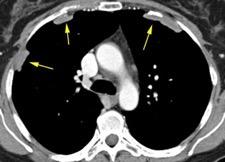

Atropellado. Neumotórax bilateral.

TC: contusión pulmonar severa. Enfisema subcutáneo. Signo del surco profundo

Visible en radiografías en decúbito supino de los pacientes con neumotórax por la acumulación de aire en el seno costofrénico.

“Deep sulcus sign”. Seno costofrénico aumentado en anchura y profundidad